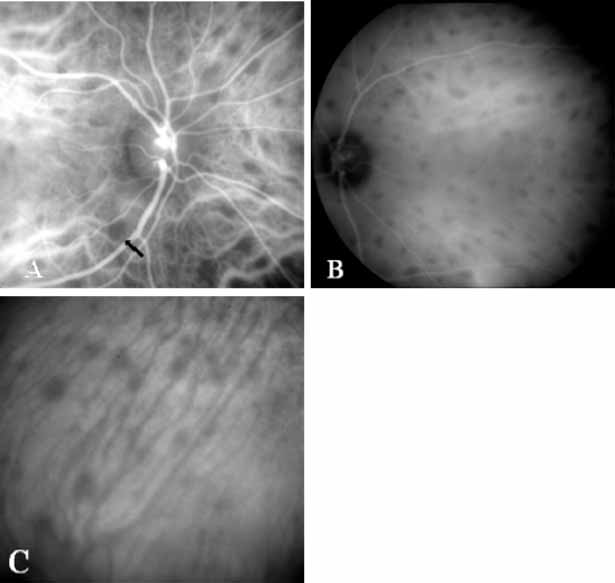

More recently, ICG angiography has begun to play an important role in the management of patients with occult CNV. In particular, the identification and management of two subsets of occult CNV, namely retinal angiomatous proliferation (RAP)34 and polypoidal choroidal neovascularization (PCV),35 are greatly enhanced with ICG angiography. RAP is a distinct subgroup of neovascular AMD in which angiomatous proliferation within the retina is the first manifestation of the process of neovascularization. As the neovascularization proliferates into the outer retina and subretinal space, the angiomatous proliferation is then surrounded by dilated retinal vessels, hemorrhages (preretinal, intraretinal, and subretinal), and exudates. One or more of the related, compensatory retinal vessels perfuse and drain the neovascularization, occasionally forming a retinal–retinal anastomosis (RRA). In these patients, the same indistinct staining seen in occult CNV is present on a fluorescein angiogram. Therefore, most cases of RAP require the use of ICG angiography to make the diagnosis (Fig. 11).34

ICG angiograms of RAP lesions reveal a focal area of intense hyperfluorescence corresponding to a so-called hot-spot of neovascularization with some late extension of the leakage within the retina caused by intraretinal neovascularization (IRN) within the deep layers of the retina. As the IRN progresses down into the subretinal space, the neovascularization present in the choroid joins the IRN to form a large, neovascular complex. At this stage, clinical and angiographic evidence of a vascularized PED (V-PED) is often present. ICG is the preferred method of imaging a V-PED because the serous component of the PED remains hypofluorescent while the vascular component displays hyperfluorescence. ICG angiography may be able to capture direct communication between the retinal and choroidal component of the neovascular complex as they meet to form a retinal choroidal anastomosis (RCA).34 Treatment options of RAP lesions include: traditional laser photocoagulation of the stage 1 and early stage 2 lesions, surgical excision of stage 2 lesions in conjunction with laser diathermy, as well as PDT, alone and in combination with other treatments, particularly triamcinolone acetonide.36,37 Other therapies, both singly and in combination, are currently undergoing investigation for this unique form of neovascular AMD.

Although initially reported exclusively in middle-aged, black females, PCV has since been recognized as a variant of CNV that can be found in all patients with AMD. This entity is characterized by the presence of an inner choroidal vascular network ending in an aneurysmal bulge clinically seen as a red–orange, spheroid, polyp-like structure. Leakage and bleeding from the choroidal vascular abnormalities result in multiple, recurrent, serosanguinous RPE detachments.25,39,40,41 ICG can be used to identify and characterize the vascular abnormality with high sensitivity and specificity.19–21,40–59 Early-phase images of the lesions show a distinct network of vessels within the choroid. Patients with juxtapapillary involvement show a radial, arching pattern with an inner network of vascular channels extending and connecting with smaller, spanning branches that are more numerous and increasingly prominent at the edge of the PCV lesion.

Larger choroidal vessels in the PCV lesion begin to fill before retinal vessels but appear to fill at a slower rate than the retinal vessels. The lesion initially appears noticeably hypofluorescent relative to the surrounding, uninvolved choroid, but soon after the network is first visible with ICG angiography, small, hyperfluorescent “polyps” can be seen within the choroid. These polypoidal structures correspond to the red–orange choroidal excrescence seen clinically. They leak slowly into the surrounding hypofluorescent area, creating increasing hyperfluorescence. In the late phases of the ICG angiogram, a uniform washout pattern is seen as the dye disappears from the polypoidal vascular structure; the late-staining characteristic of occult CNV is not seen in PCV. PCV may be localized to the macular area without any peripapillary involvement. It may present as a network of small branching vessels ending in polypoidal dilation best-imaged with ICG angiography. (Fig. 12)